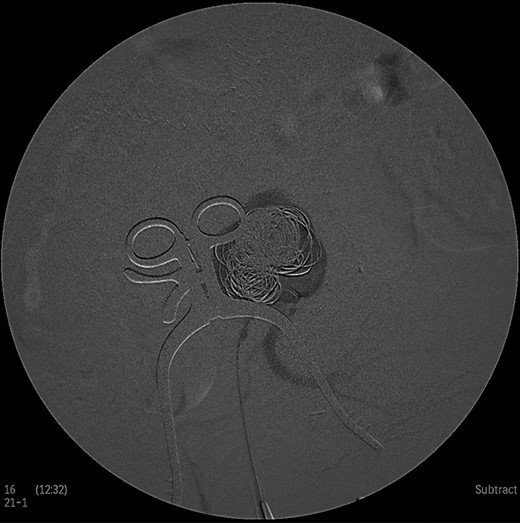

Under general anesthesia the patient was placed in prone position and a 15 cm transverse incision, slightly curvy was performed in the middle part of the right gluteal region between the posterior superior iliac spine and ischiac tuberosity. The gluteus maximus muscle was split and the inferior gluteal artery was identified as it entered the gluteal region through the greater schiatic foramen near the schiatic nerve below the piriformis muscle. The inferior gluteal artery was punctured using Seldinger technique and a 4Fr was introduced into the artery (Fig. 2). An angiography was made revealing the aneurysm of the right IIA and two feeding arteries, inferior gluteal artery and probably a branch of superior gluteal artery, filling the sac (Fig. 3). A 0.014 inch Pilot guide wire (Boston Scientific Corporation, USA) was inserted into the aneurysm and a microcatheter 3 Fr RENEGADE STC (Boston Scientific Corporation, USA) was advanced over the wire. After removing the wire, embolization microcoils (Interlock, Boston Scientific, USA) (two coils 22–600 mm, two coils 20–500 mm, three coils 18–500 mm) were introduced into the aneurysm sac (Fig. 4). A 5 Fr sheath was subsequently placed, a 5Fr RIM catheter (Cordis, USA) was advanced to the aneurysm sac through a 0.035 inch Terumo guide wire (Glidewire, Terumo Corporation, Japan) and selective catheterization of the second feeding artery was performed (Fig. 5). Embolization coils (Interlock, Boston Scientific, USA) were inserted into the two feeding arteries (two coils 15–400 mm) (Fig. 6). Completion angiogram depicted absence of blood flow into the aneurysm and the runoff vessels (Fig. 7). The patient had an uneventful recovery period without buttock claudication, ischemic complications and discharged in good condition. A follow-up CT aortography after 6 months depicted complete thrombosis of the aneurysm (Fig. 8).

Intraoperative angiogram showing the presence of the aneurysm and two collateral vessels, embolization with coils of the sac and two feeding arteries. Completion angiogram depicted absence of blood flow in the IIA aneurysm and the runoff arteries.